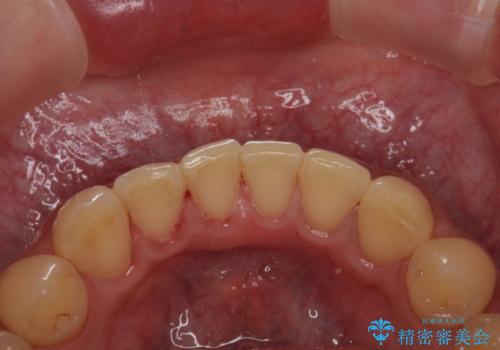

- 茶渋がついて歯の汚れが気になり、きれいにしたいと希望されました。

PMTC(30分コース) 担当衛生士 進藤

着色だけでなく、歯の汚れもとれてツルツルになり気持ちがいいと

喜んでいただけました。